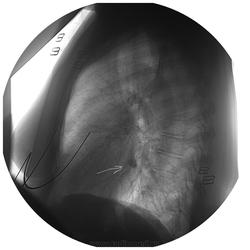

Уважаемые коллеги! Хотелось бы Вашего мнения. R-гр. ОГК в 2 проекциях - в правом корне доп. тень? Да, и прошу не удивляться "круглым" снимкам - вот так снимают у нас...

Мой вариант - сосуд в ортопроекции. И, опять-таки, на мой взгляд, на снимках в прямой и боковой проекциях указаны разные отделы.

Да, по прямой, ортоград...А вот то что на боковой, так то нуждается минимум в линеечке.

Согласен с сосудом. И на прямой он. И на боковой. Тоже он - сосуд. Но уже другой!) Посмотрите по взаиморасположению - относительно пространственных ориентиров - той же аорты (верхнего края дуги) - сосуд так интересно не меняет своё местонахождение, пусть и при различном объёме воздуха у пациента в груди.